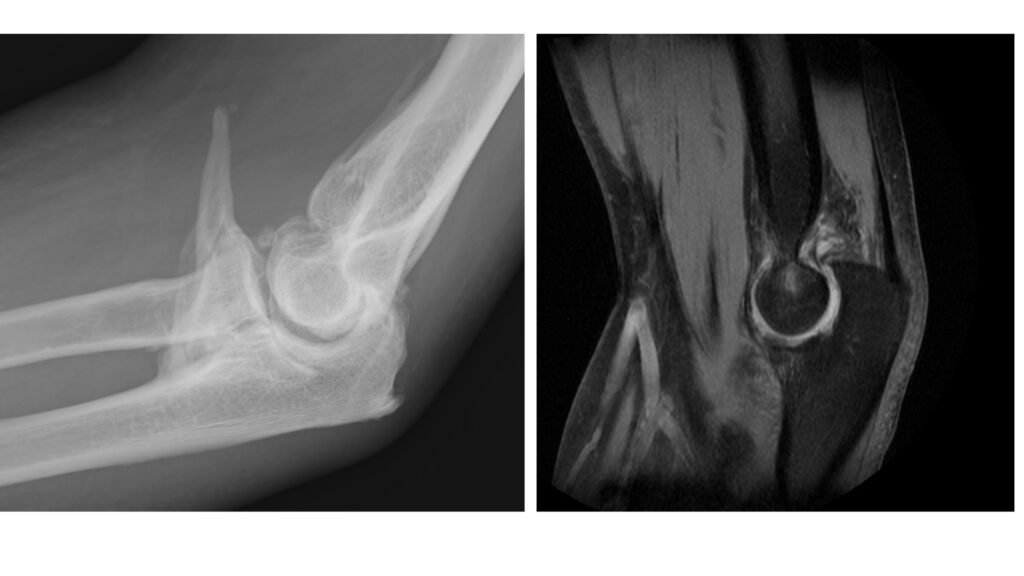

- Cicatrización excesiva: algunos pacientes desarrollan tejido cicatricial duro o incluso hueso dentro de la articulación (osificación heterotópica).

- Cirugía abierta en casos más complejos (con cicatrices, placas o tornillos previos, osificación, etc.).